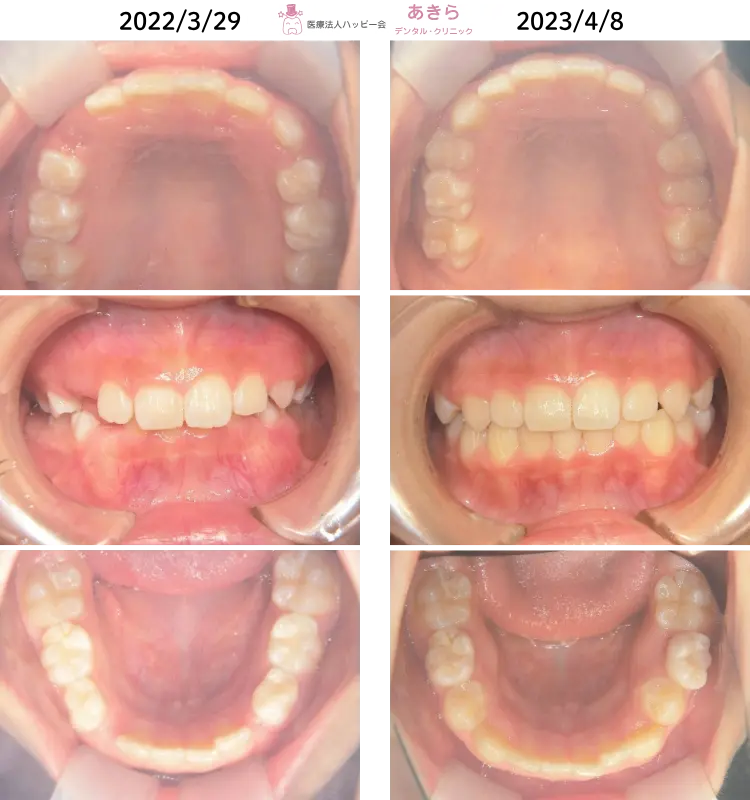

SH療法

SH療法-症例-No.014-左上5番の口蓋側転移位を伴なう症例

山形市の歯医者「あきらデンタル・クリニック」のSH療法の症例をご紹介します。 SH… -